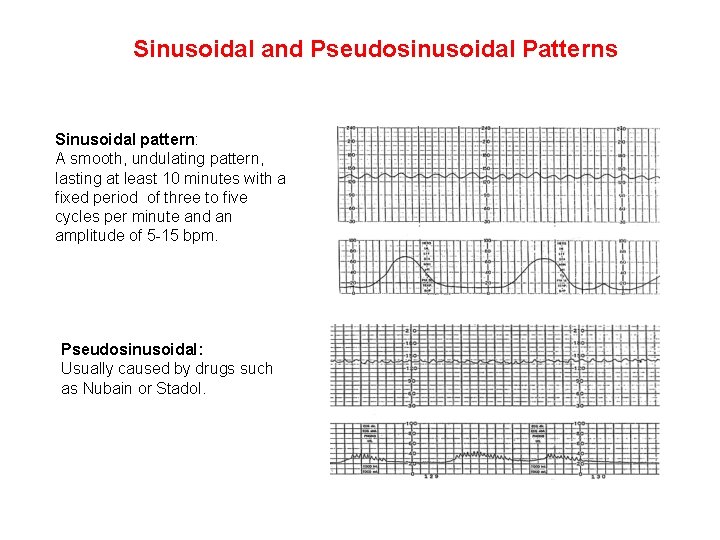

Sinusoidal and Pseudosinusoidal Patterns Sinusoidal pattern: A smooth, undulating pattern, lasting at least 10 minutes with a fixed period of three to five cycles per minute and an amplitude of 5 -15 bpm. Pseudosinusoidal: Usually caused by drugs such as Nubain or Stadol.